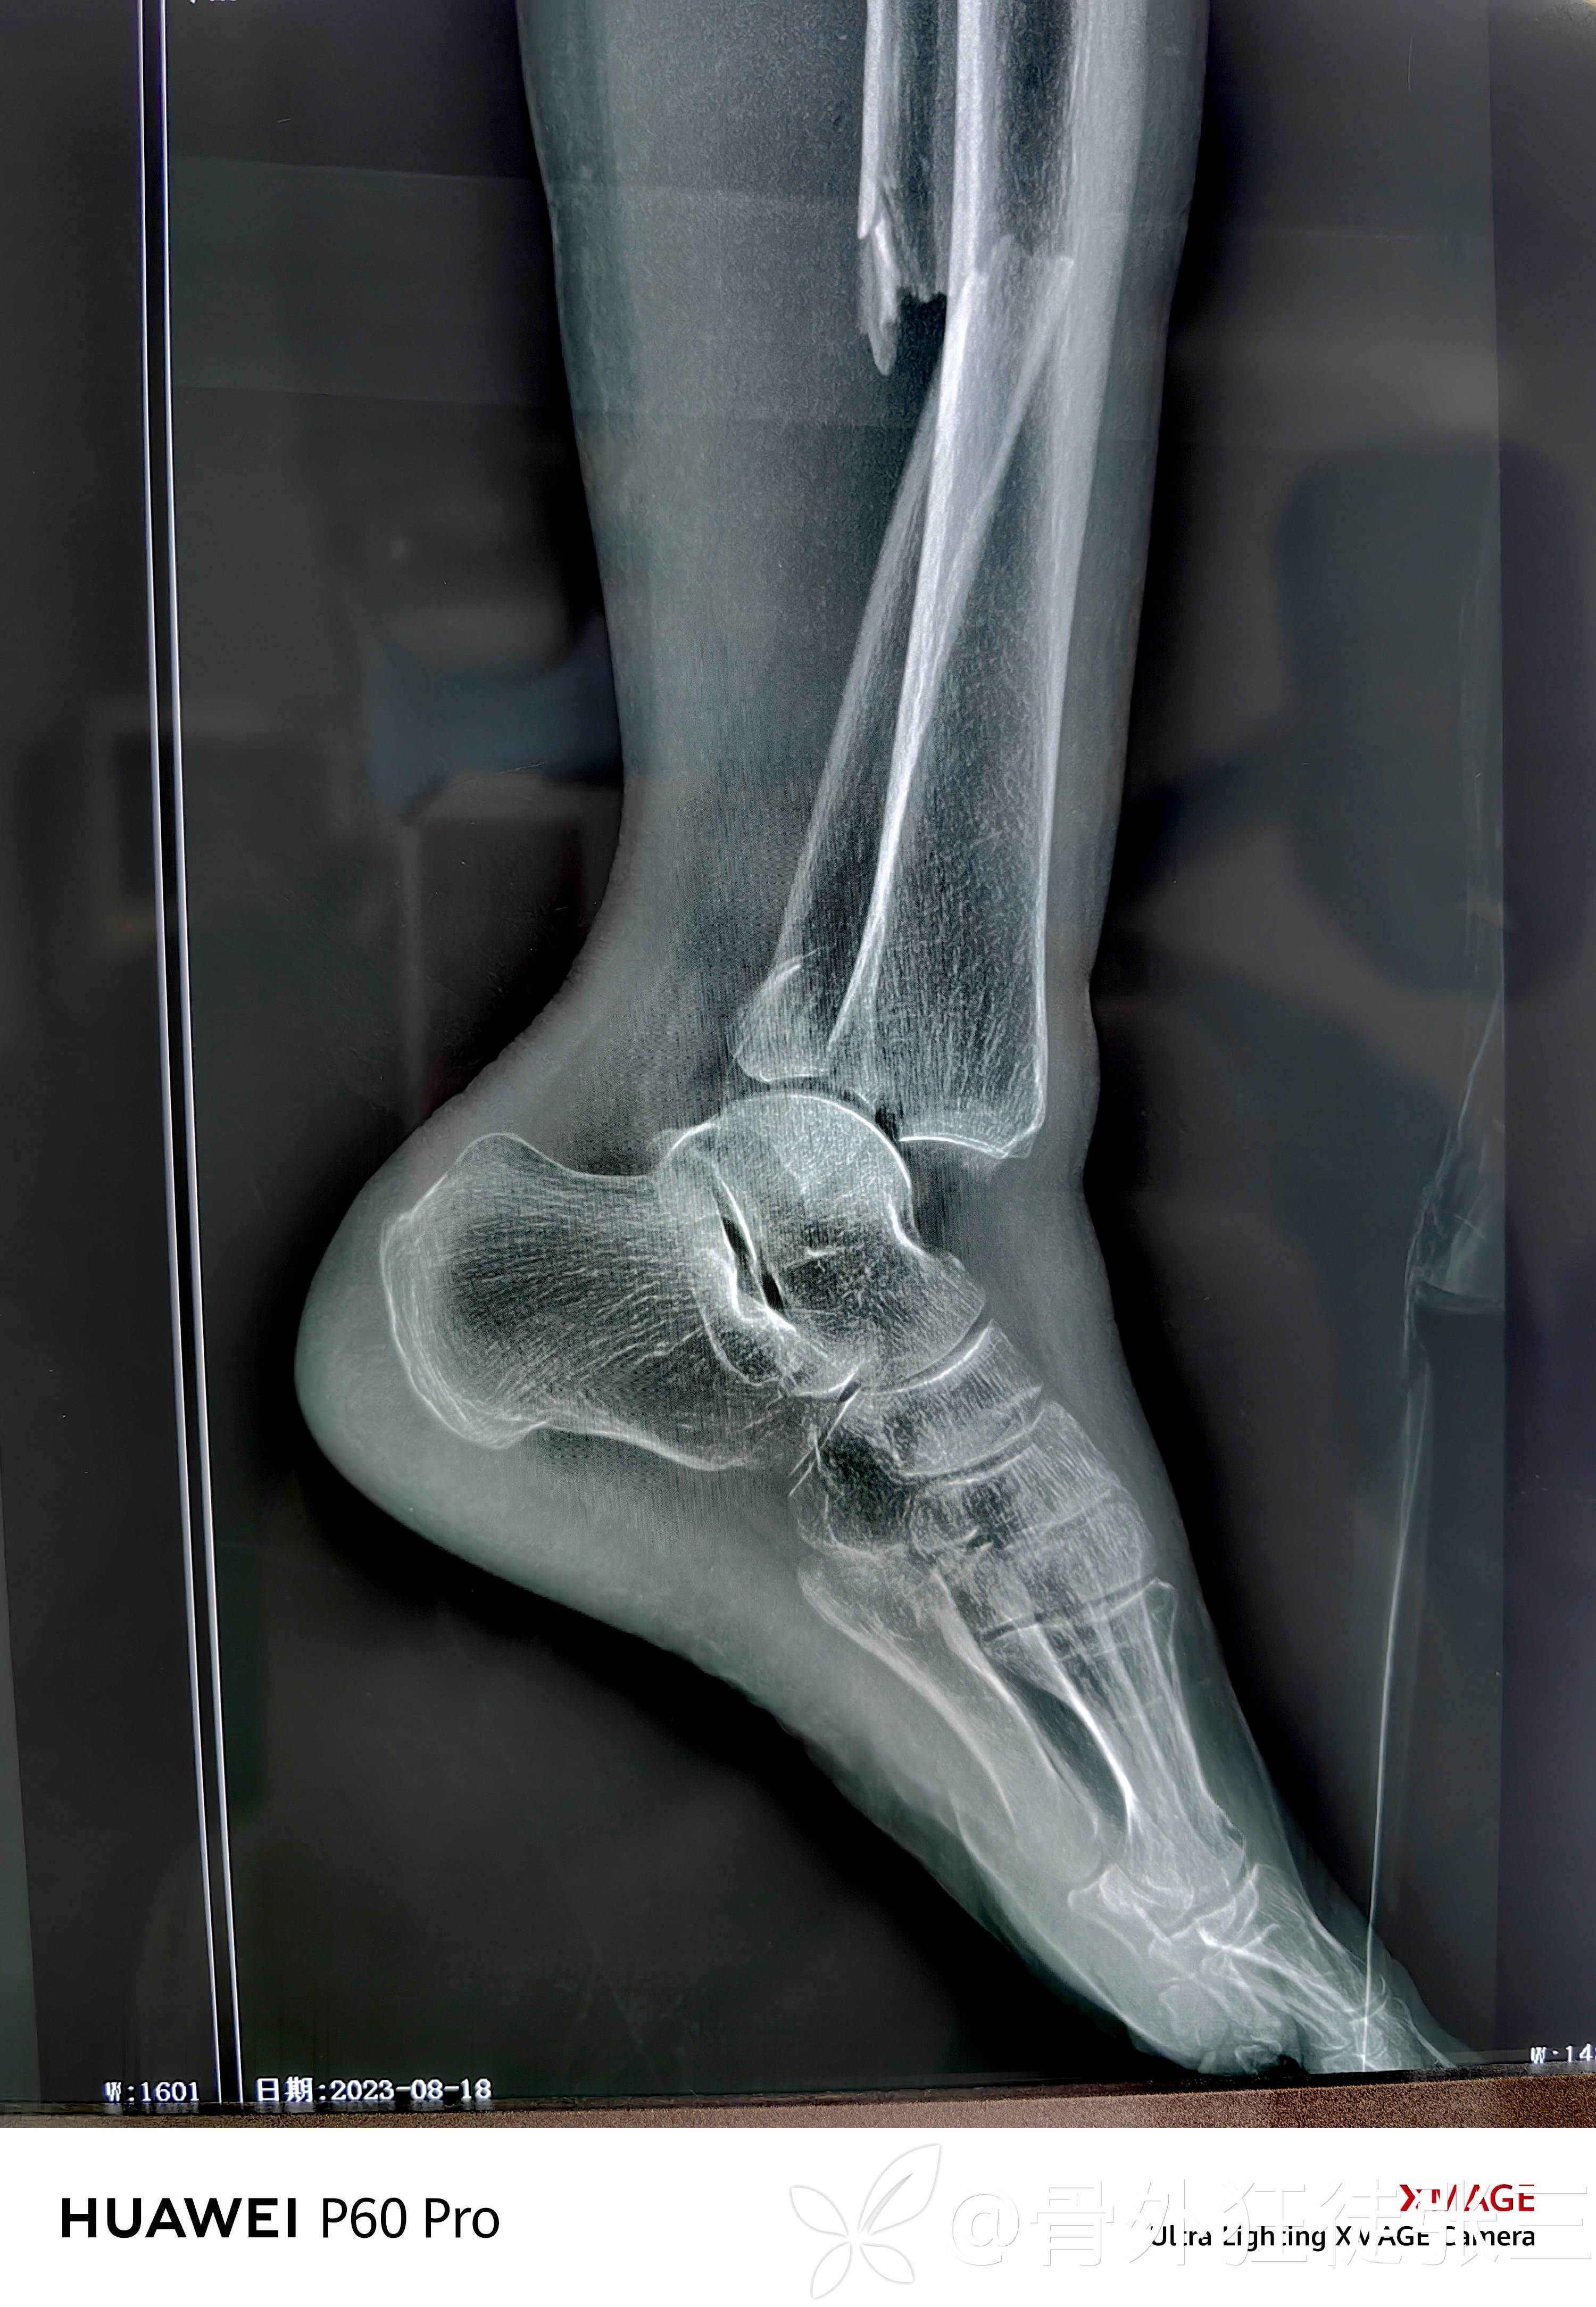

旋前外旋四期踝关节骨折脱位一例

患者性别:女

患者年龄:68岁

主诉:车祸致左踝关节疼痛、畸形、活动受限3小时。

辅助检查:

高位腓骨粉碎性骨折

内踝+后踝骨折

下胫腓分离

内踝骨折,胫距关节脱位